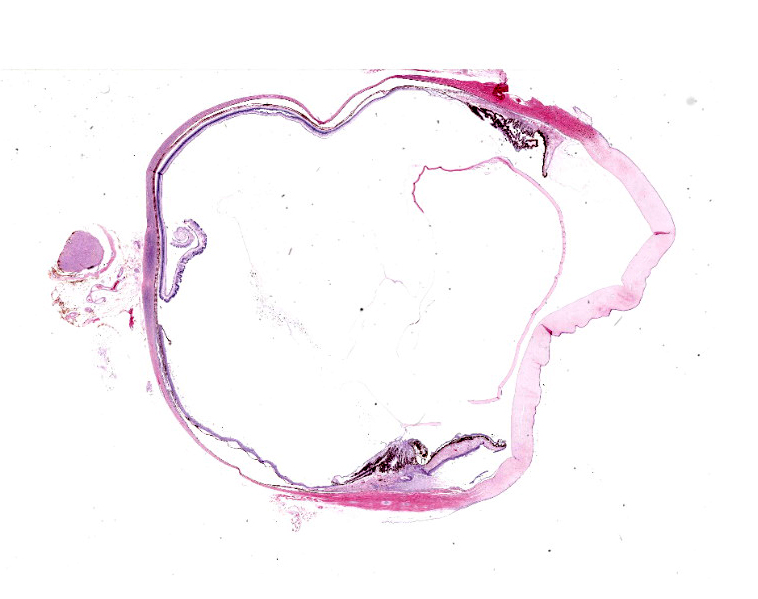

Eye: Overlying the corneal endothelium, anterior and posterior iris, portions of the lens epithelium, and the inner surface of the retina, as well as effacing and replacing the ciliary body, and occluding the drainage angle is an unencapsulated, densely cellular, infiltrative, neoplasm composed of epithelial cells arranged in broad dense cords on a moderate fibrovascular stroma. Neoplastic cells are polygonal with distinct cell borders, pronounced intercellular bridging, a moderate amount of pale eosinophilic cytoplasm, and irregularly round to vesiculate nuclei, with up to three distinct nucleoli. Anisocytosis and anisokaryosis is moderate. The mitotic rate is high with up to 12 mitotic figures per ten 40x HPF. Multifocally, neoplastic cells exhibit squamous differentiation. Near the optic nerve, the neoplastic cells invade the vascular and fibrous tunics, elevating and dissecting beneath the retinal pigment epithelium under a detached and coiled degenerate retina. At the caudal interior surface of the globe, there are numerous neutrophils admixed with abundant eosinophilic cellular and karyorrhectic debris and neoplastic cells infiltrate into the retinal vasculature.Contributor's Morphologic Diagnoses:

This case contributor gives a thorough review of intraocular neoplasms in cats, touching on many major points of discussion during review of this case. Conference participants were readily able to reach a diagnosis of metastatic carcinoma, but not all were convinced that this was a metastatic squamous cell carcinoma (SCC) due to the lack of dyskeratosis within neoplastic epithelial cells, coupled with the lack of a primary mass found during workup. The prominent intercellular bridging between the neoplastic cells was noted by all, which can be a major feature of SCC; and squamous cell carcinomas are common tumors of the feline head; however other participants felt strongly that they could not rule out a carcinoma of other origin based on histology alone. For this reason, a morphologic diagnosis of “metastatic carcinoma” was ultimately favored by participants in this case due to the lack of clear-cut evidence of a squamous cell carcinoma on the H&E.There was no argument to be found on whether this was primary or metastatic, as the histologic evidence was strongly supportive of a metastatic process (i.e., the neoplasm primarily found within the highly vascular choroid and uvea, intravascular neoplastic cell emboli, etc.). The secondary changes in the eye were also discussed and it was concluded that this eye had glaucoma secondary to the neoplasm, evidenced by the retinal ganglion cell degeneration and loss with tapetal sparing, occlusion of the drainage angles by both the neoplasm and inflammation, buphthalmia (enlarged globe, attenuated and degenerative corneal epithelium, scleral thinning), and perivascular edema of the aqueous veins that drain the trabecular meshwork of the drainage angle.